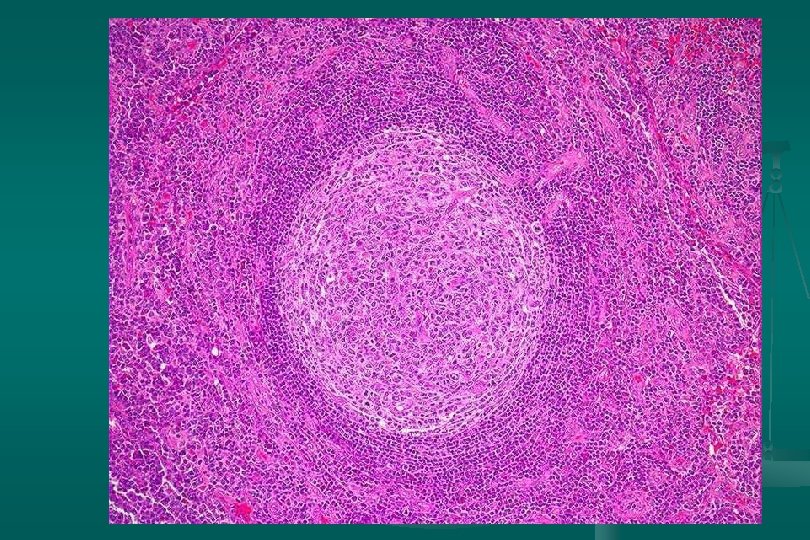

Enfermedad de Castleman Histología: dos categorías: 1. Tipo vascular hialino (angiofolicular): n Folículos grandes, proliferación vascular y hialinización central. n Capas concéntricas de linfocitos en la periferia del folículo (capas de cebolla). n Estroma interfolicular: prominente, venulas poscapilares hiperplásicas, CP, E. inmunoblastos n

Enfermedad de Castleman Subtipo linfoide: *Expansión zona del manto *Centros germinales pequeños. 2. Tipo células plasmáticas: n Proliferación difusa de cels plasm interfolicular + cuerpos de Russell n Cambio vascular-hialino: ausente n Depósito de material acidofílico amorfo (fibrina y complejos inmunes) n